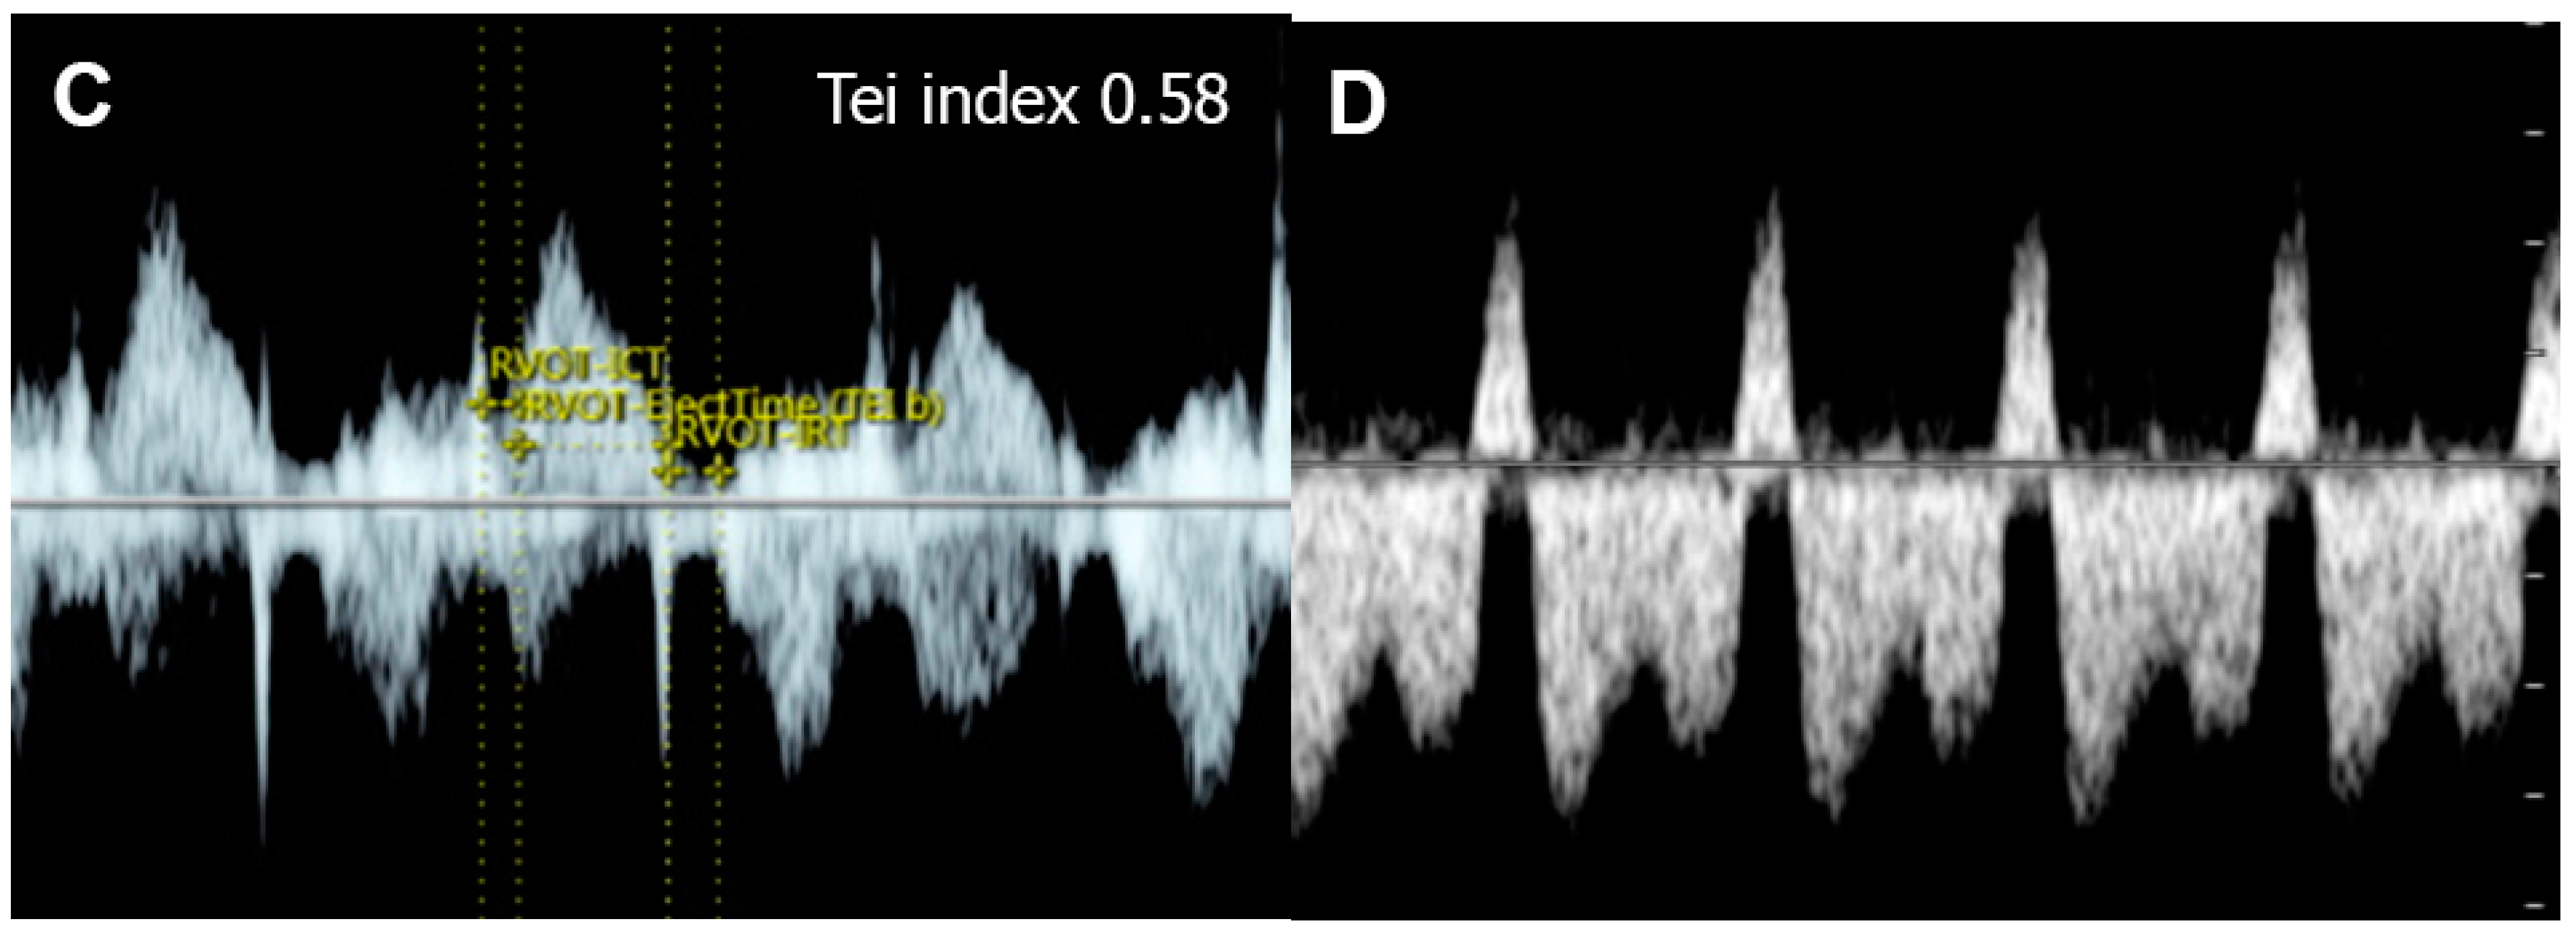

5.6. Critical Aortic Stenosis

- Mäkikallio, K.; McElhinney, D.B.; Levine, J.C.; Marx, G.R.; Colan, S.D.; Marshall, A.C.; Lock, J.E.; Marcus, E.N.; Tworetzky, W. Fetal aortic valve stenosis and the evolution of hypoplastic left heart syndrome: Patient selection for fetal intervention. Circulation 2006, 113, 1401–1405. [Google Scholar] [CrossRef]

- McElhinney, D.B.; Vogel, M.; Benson, C.B.; Marshall, A.C.; Wilkins-Haug, L.E.; Silva, V.; Tworetzky, W. Assessment of left ventricular endocardial fibroelastosis in fetuses with aortic stenosis and evolving hypoplastic left heart syndrome. Am. J. Cardiol. 2010, 106, 1792–1797. [Google Scholar] [CrossRef]

- Selamet Tierney, E.S.; Wald, R.M.; McElhinney, D.B.; Marshall, A.C.; Benson, C.B.; Colan, S.D.; Marcus, E.N.; Marx, G.R.; Levine, J.C.; Wilkins-Haug, L.; et al. Changes in left heart hemodynamics after technically successful in-utero aortic valvuloplasty. Ultrasound Obstet. Gynecol. 2007, 30, 715–720. [Google Scholar] [CrossRef]

- Tulzer, A.; Arzt, W.; Gitter, R.; Sames-Dolzer, E.; Kreuzer, M.; Mair, R.; Tulzer, G. Valvuloplasty in 103 fetuses with critical aortic stenosis: Outcome and new predictors for postnatal circulation. Ultrasound Obstet. Gynecol. 2022, 59, 633–641. [Google Scholar] [CrossRef]